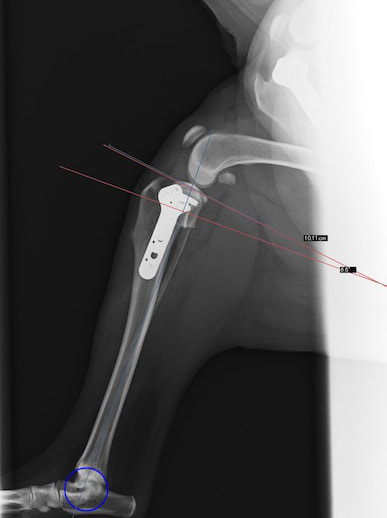

・術後レントゲン

手術前TPA 28.4° が術後TPA 11.7° に矯正されました。

術前TPA計測

術後TPA計測